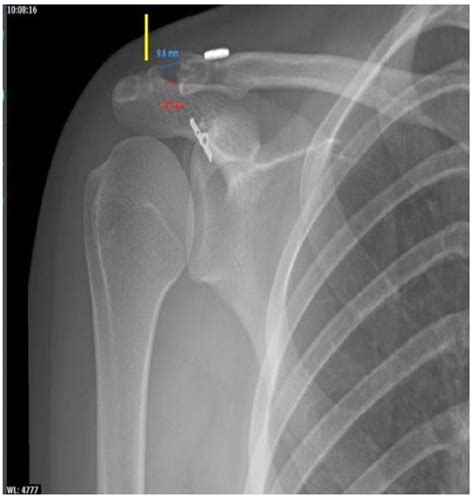

• Monitoring Progress: For patients undergoing treatment, follow-up X-rays can monitor the healing process and ensure that the treatment is effective.

• Surgery: In severe cases, surgical intervention may be necessary to repair the joint.

• Treatment Plan: Follow the recommended treatment plan, which may include rest, medication, physical therapy, or surgery.

• Monitor Progress: Attend all follow-up appointments to monitor your progress and make any necessary adjustments to the treatment plan.